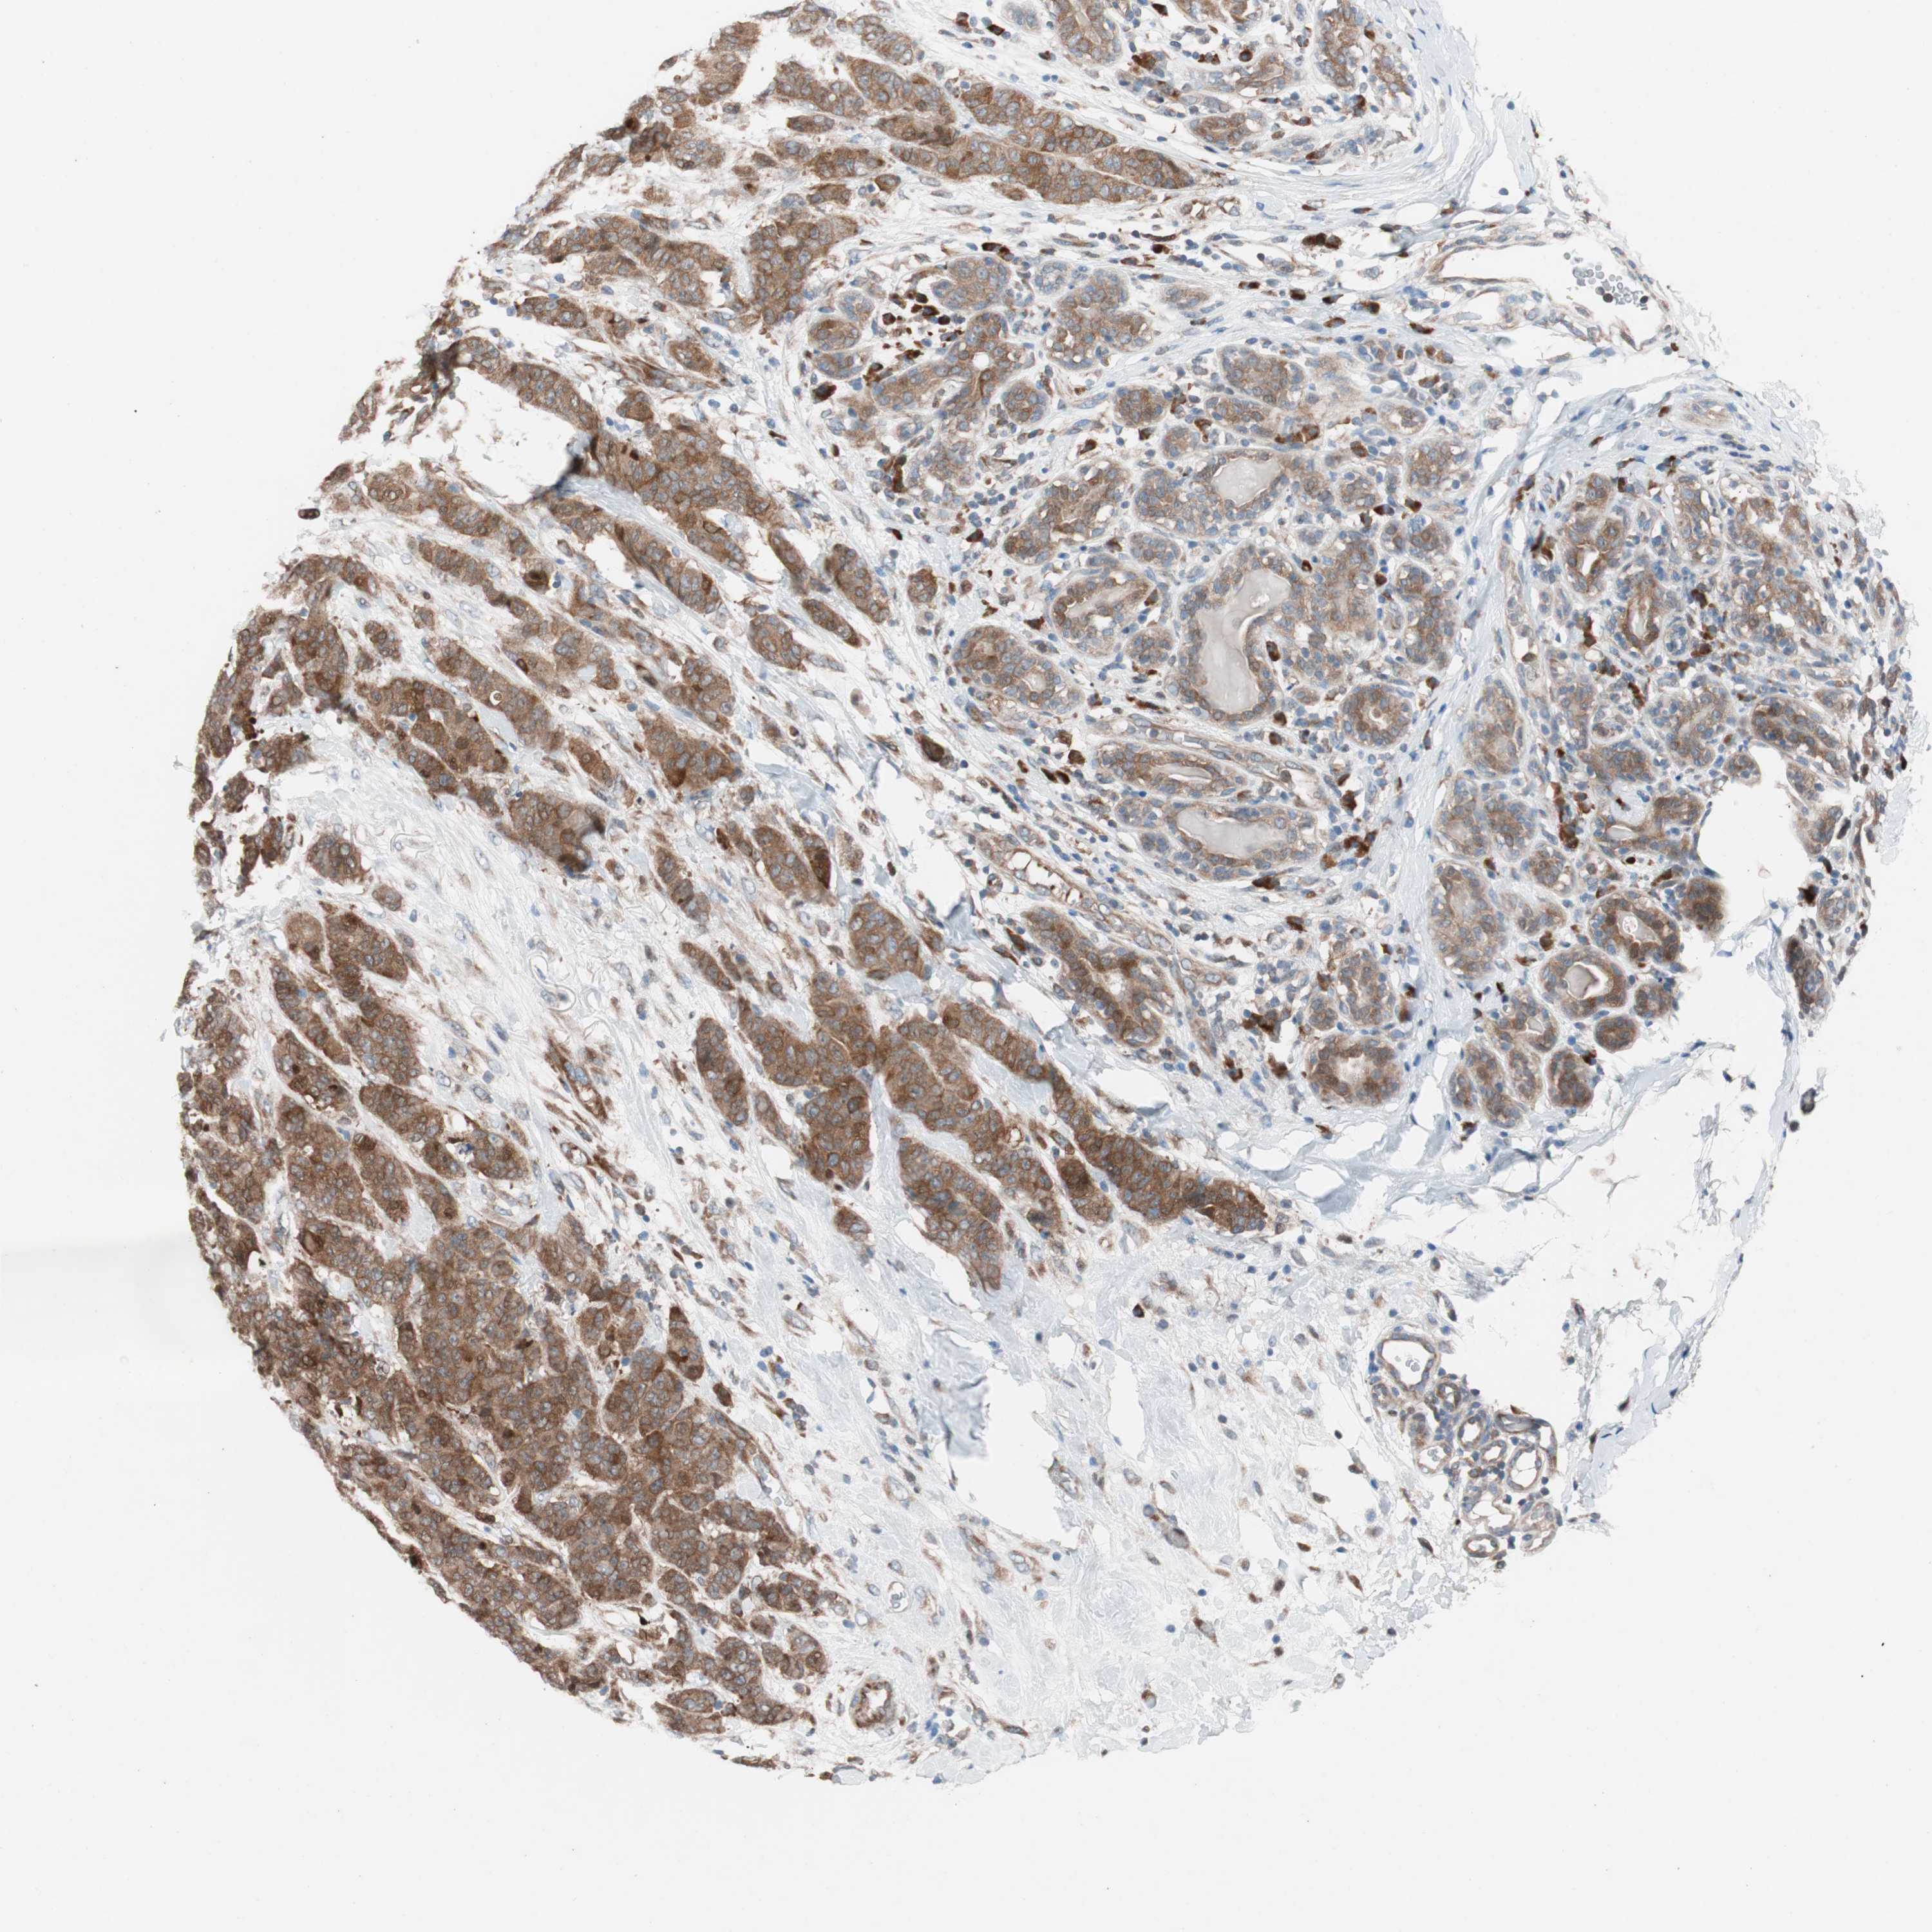

CANCER BREAST CANCER Show tissue menu

BRCA TCGA BRCA VALIDATION PROTEIN EXPRESSION